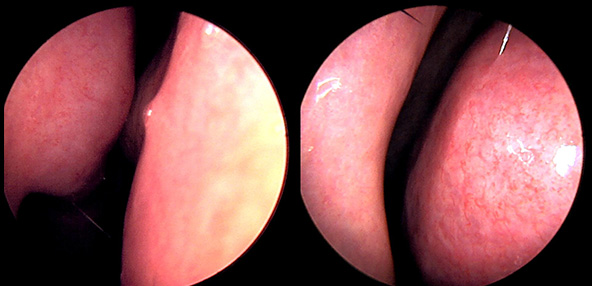

※ 비중격 비염 수술 후 생길 수 있는 부작용으로는 출혈, 감염, 염증이 있을 수 있습니다.

본 사진은 의료기관에서 진료를 본 환자이고, 전후 사진 인물이 동일인이며,동일조건에서 촬영이 되었습니다.